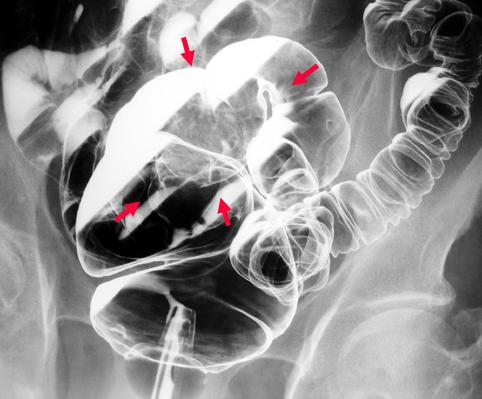

Criteria of Hist.ClassificationMalignant epithelial tumor/Mucinous carcinoma

LocationLarge intestine(Colon)/Rectum

Technique, MethodX-ray

Macroscopic TypesType 1 Protuberant (polypoed) type/

Size40 -

Depth of Tumor Invasionsubserosa (subadventitia)